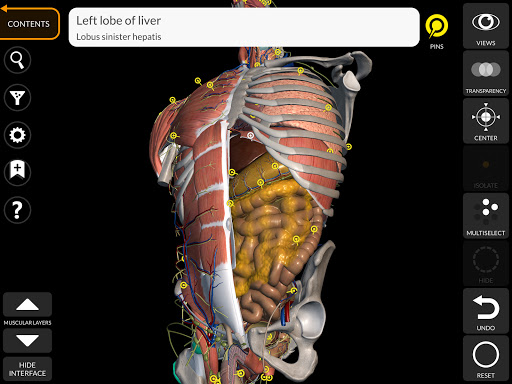

"Anatomía - Atlas 3D" permite estudiar la anatomía humana de forma fácil e interactiva.

A través de una interfaz sencilla e intuitiva es posible observar cada estructura anatómica desde cualquier ángulo.

Los modelos anatómicos 3D son especialmente detallados y con texturas de hasta una resolución de 4k.

La subdivisión por regiones y las vistas predefinidas facilitan la observación y el estudio de partes individuales o grupos de sistemas y las relaciones entre los diferentes órganos.

MODELOS ANATÓMICOS 3D

nervioso • Sistema respiratorio • Sistema digestivo • Sistema urogenital (masculino y femenino) • Sistema endocrino • Sistema linfático • Sistema ocular y auditivo CARACTERÍSTICAS • Interfaz sencilla e intuitiva • Rotar y hacer zoom en cada modelo en el espacio 3D • Opción para ocultar o aislar uno o varios modelos seleccionados • Filtro para ocultar o mostrar cada sistema • Función de búsqueda para encontrar fácilmente cada parte anatómica • Función de marcador para guardar vistas personalizadas • Rotación inteligente que mueve el centro de rotación automáticamente • Función de transparencia • Visualización de músculos a través de niveles de capas desde las superficiales hasta las más profundas • Al seleccionar un modelo o un pin, aparece el término anatómico relacionado • Descripción de los músculos: origen, inserción, inervación y acción • Mostrar/ocultar interfaz de usuario (muy útil con pantallas pequeñas) MULTILINGÜE • Los términos anatómicos y la interfaz de usuario están disponibles en 11 idiomas: latín, inglés, francés, alemán, italiano, portugués, turco, ruso, español, Chino, japonés y coreano • Los términos anatómicos se pueden mostrar en dos idiomas simultáneamente REQUISITOS DEL SISTEMA • Android 8.0 o posterior, dispositivos con al menos 3 GB de RAM Reversi